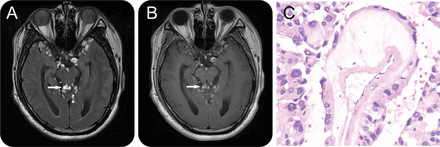

图1

脊髓室管膜瘤图像

脊柱矢状t1加权磁共振成像(a - c)演示了一个类似硬膜内的质量不均匀增强信号,从C4水平延伸至远端脊柱(白色箭头)。未发现病变仅在C1级别C3水平(A,黑色箭头)。